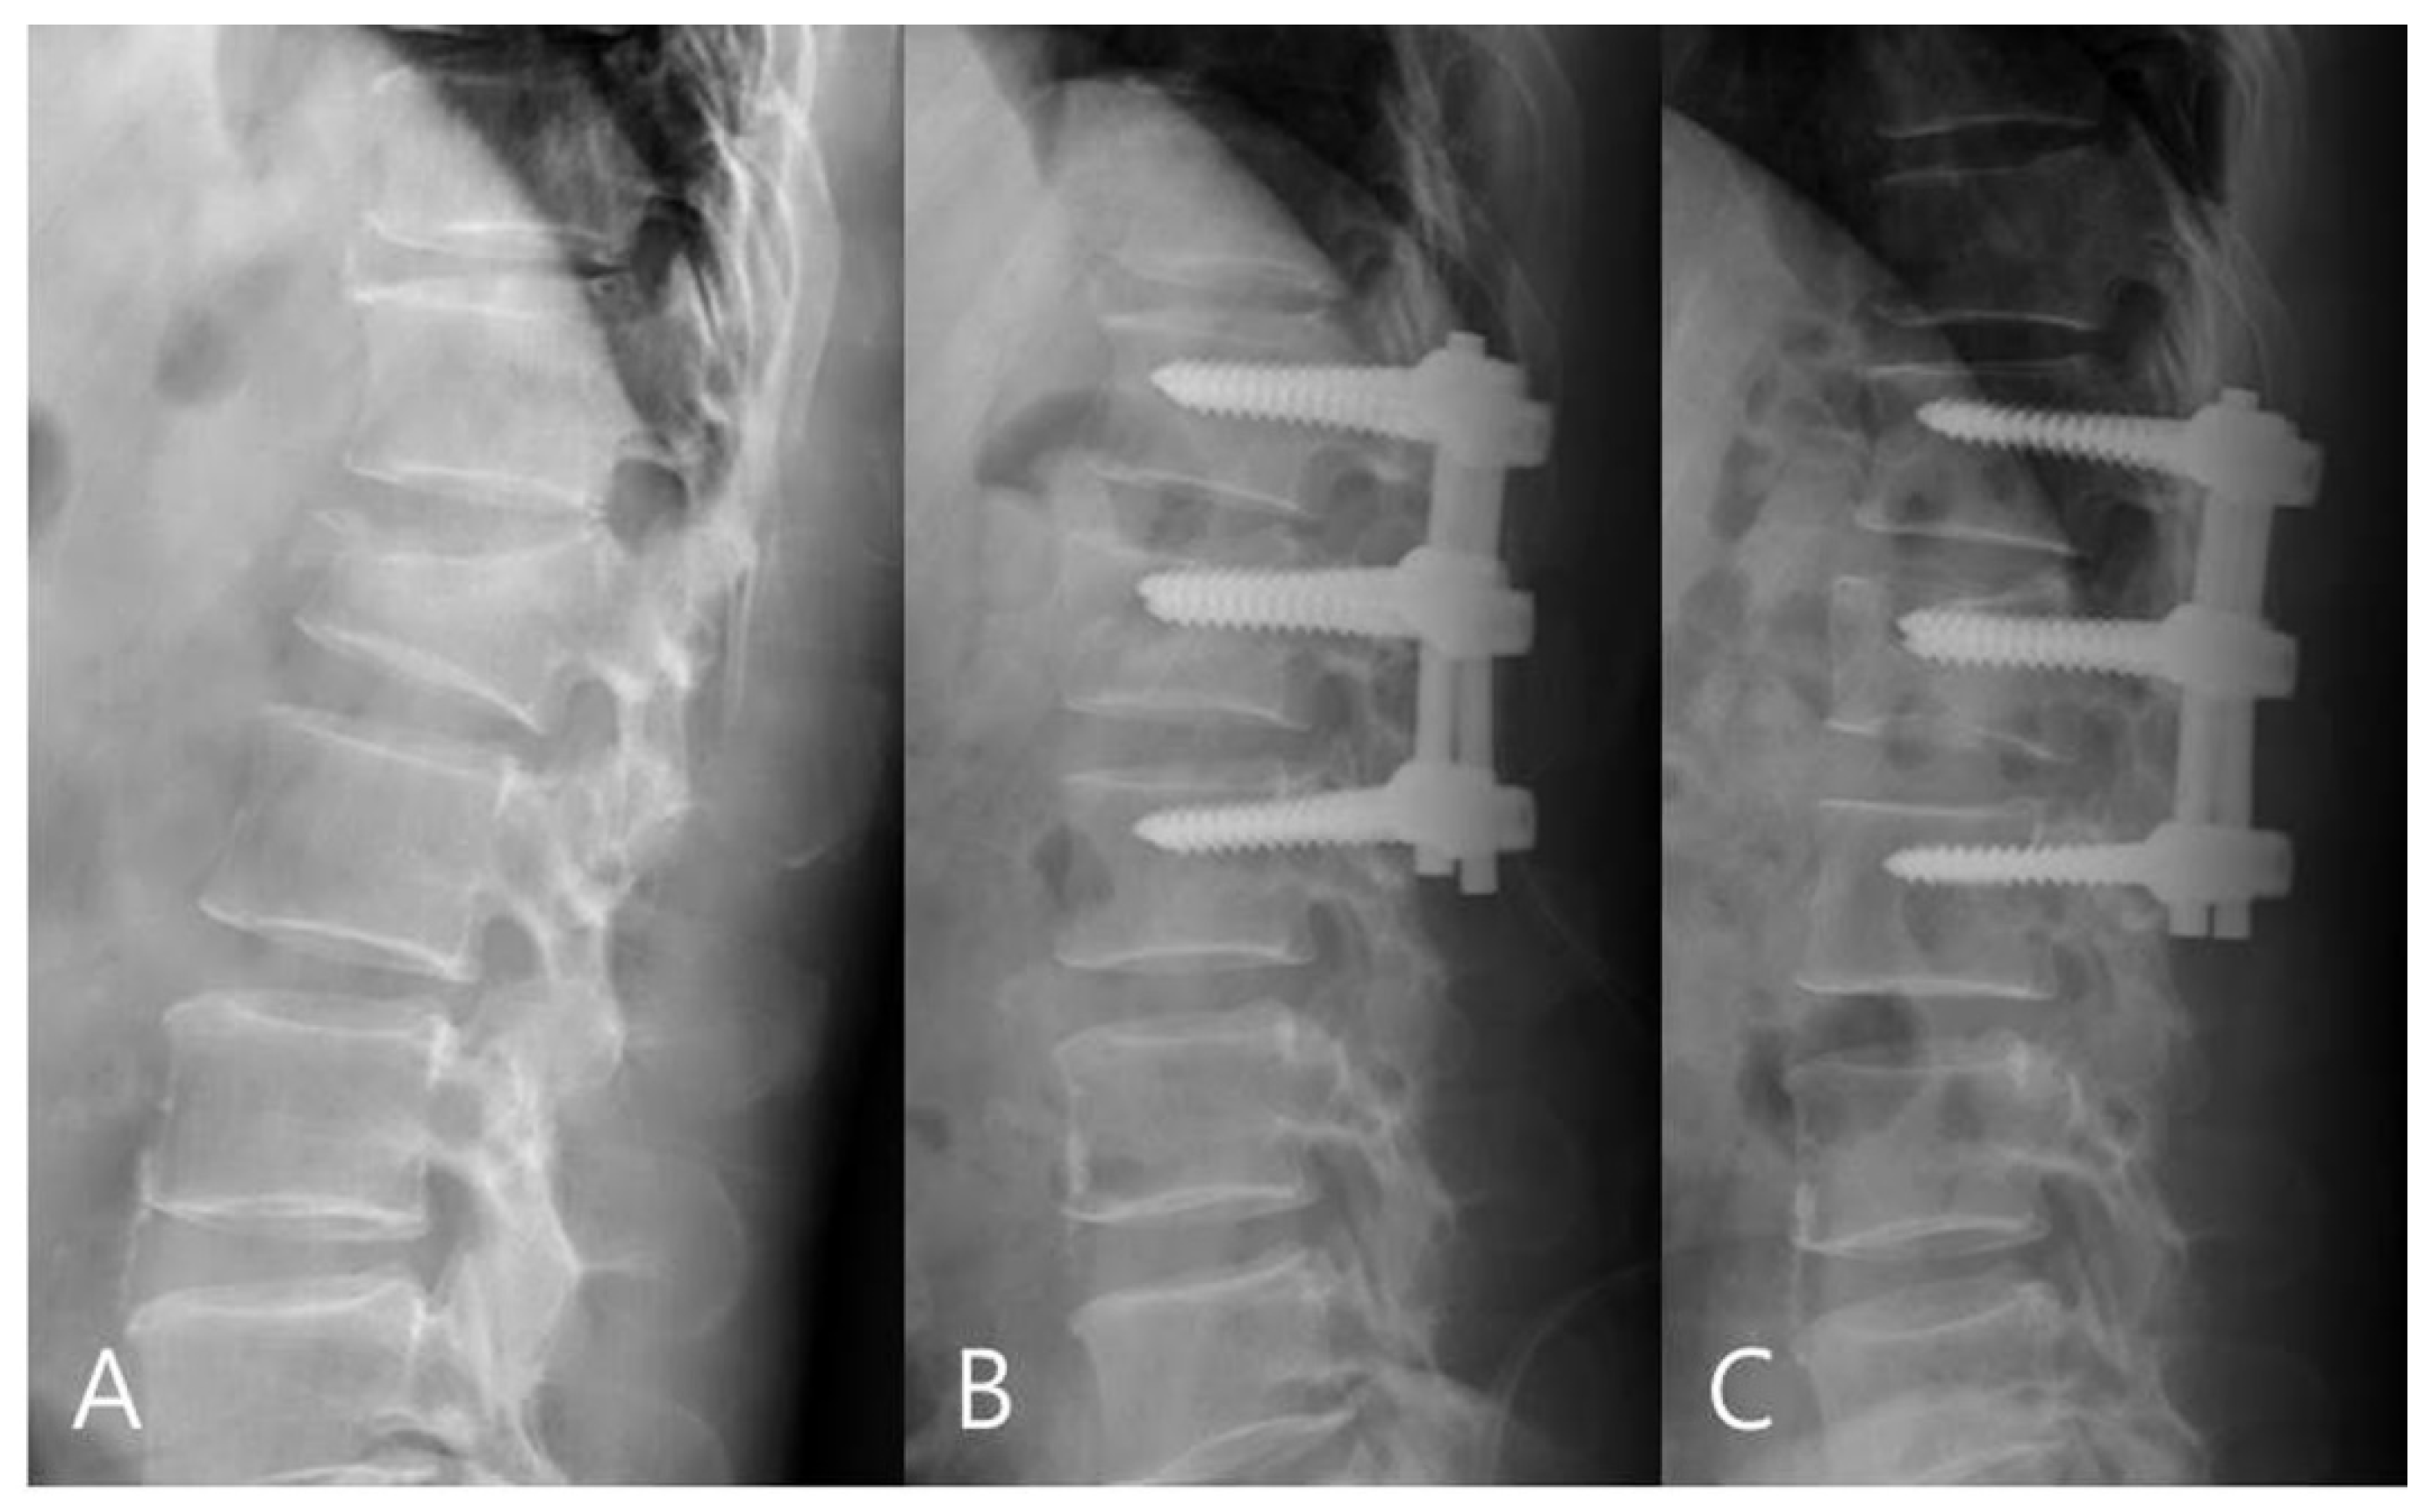

Измерение кифоза грудного отдела: Рентгеновские снимки